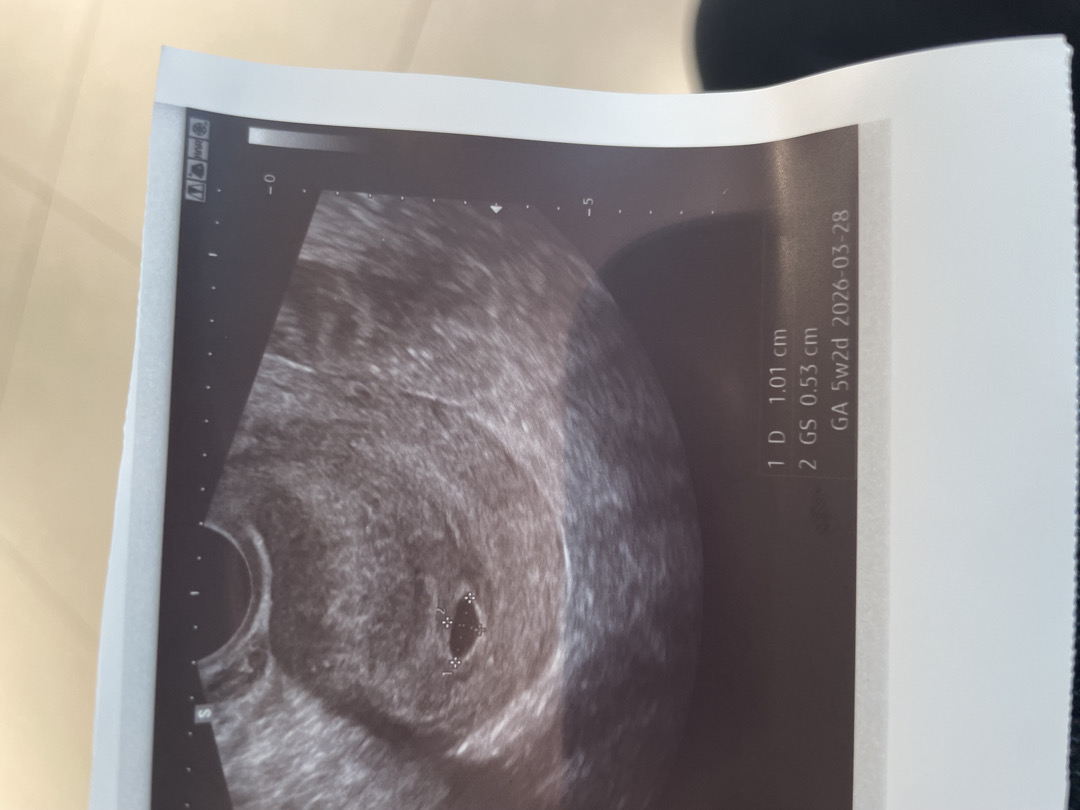

5주 2일 난황?

자연임신 막생 6/12일이고, 지난주에 아기집이 안보일수 있다고 하셨는데 크기 0.29로 보였습니다. 일주일 뒤인 오늘 갔을 때 0.53인데 난황이 안보여서 괜찮을까요?

네 보통 6주차에 난황이 보인다 하더라구요 걱정마세요~